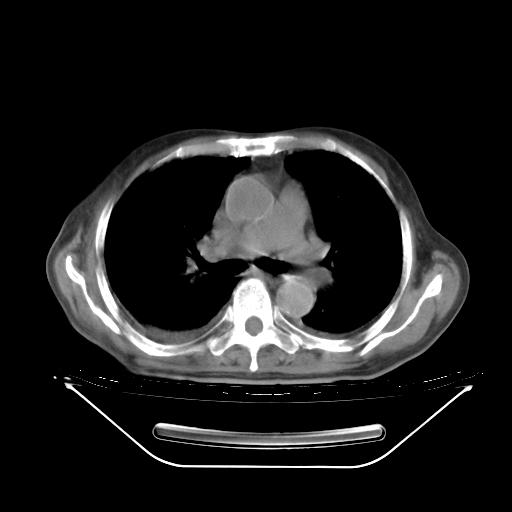

今天复查肺部CT,发现双肺广泛磨玻璃样改变。所以我把3月19日和5月9日相隔50天的肺部CT上传。请大家会诊。

2009年3月19日肺部CT片。

2009年3月19日肺部CT